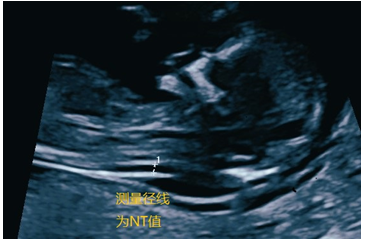

孕11-13周此时的TA初具人形,长度(头臀长)在5~8厘米,在超声下很容易被看见,而且一眼万年(图5-1)。超声下的TA展示出大体的解剖结构如颅脑、心脏、肢体,腹腔脏器等等,因此我们正式称之为胎儿。孕11-13周的胎儿非常适合进行NT(胎儿颈项透明层)的检查(图5-2),以评估胎儿患唐氏综合征的风险。

图5-2 超声测量NT值